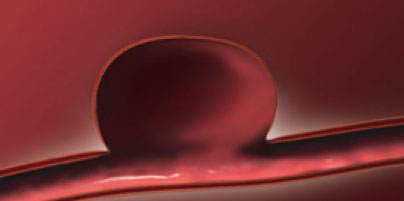

Los aneurismas cerebrales consisten en la debilidad de una pared de los vasos sanguineos que conducen la sangre hacia el cerebro, debido a la presion cronica sobre la pared debil del vaso se comienza esta a dilatar formandose una bolsa debil tal como se ilustra en la imagen anterior..

Esta bolsa tiene tendencia a romperse ocasionando asi la salida de sangre hacia el espacio por fuera de los vasos sanguineos del cerebro y en algunos casos dentro del cerebro.